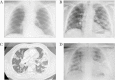

Methods: A 62-year-old man from Palamós (Spain) suffered a first mild coronavirus disease 2019 (COVID-19) episode in March 2020, confirmed by 2 independent SARS-CoV-2 nasopharyngeal polymerase chain reaction (PCR) assays and a normal radiograph. He recovered completely and tested negative on 2 consecutive PCRs. In August 2020, the patient developed a second SARS-CoV-2 infection with life-threatening bilateral pneumonia and Acute respiratory distress syndrome criteria, requiring COVID-19-specific treatment (remdesivir + dexamethasone) plus high-flow oxygen therapy. Nasopharyngeal swabs from the second episode were obtained for virus quantification by real-time PCR, for virus outgrowth and sequencing. In addition, plasma and peripheral blood mononuclear cells during the hospitalization period were used to determine SARS-CoV-2-specific humoral and T-cell responses.